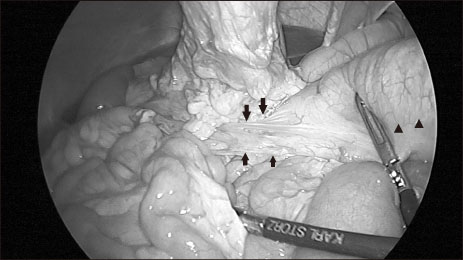

The patient experienced recurrent aspiration pneumonia and seizure one year ago. There was no problem in ingestion until aspiration pneumonia occurred, but, because of increased aspiration tendency during oral feeding, he was under nasogastric tube feeding for 1-year. For long-term management, percutaneous endoscopic gastrostomy (PEG) was planned, and an upper gastrointestinal (UGI) study was done in our institution. On UGI, the right-sided stomach was seen, and associated intestinal malrotation, without volvulus, was found (

Fig. 1). Situs anomaly was suspected for the first time since birth during this study, and PEG was performed without complications when he was 17 years old.

Fig. 1Right-sided stomach suspecting situs anomaly in upper gastrointestinal series.